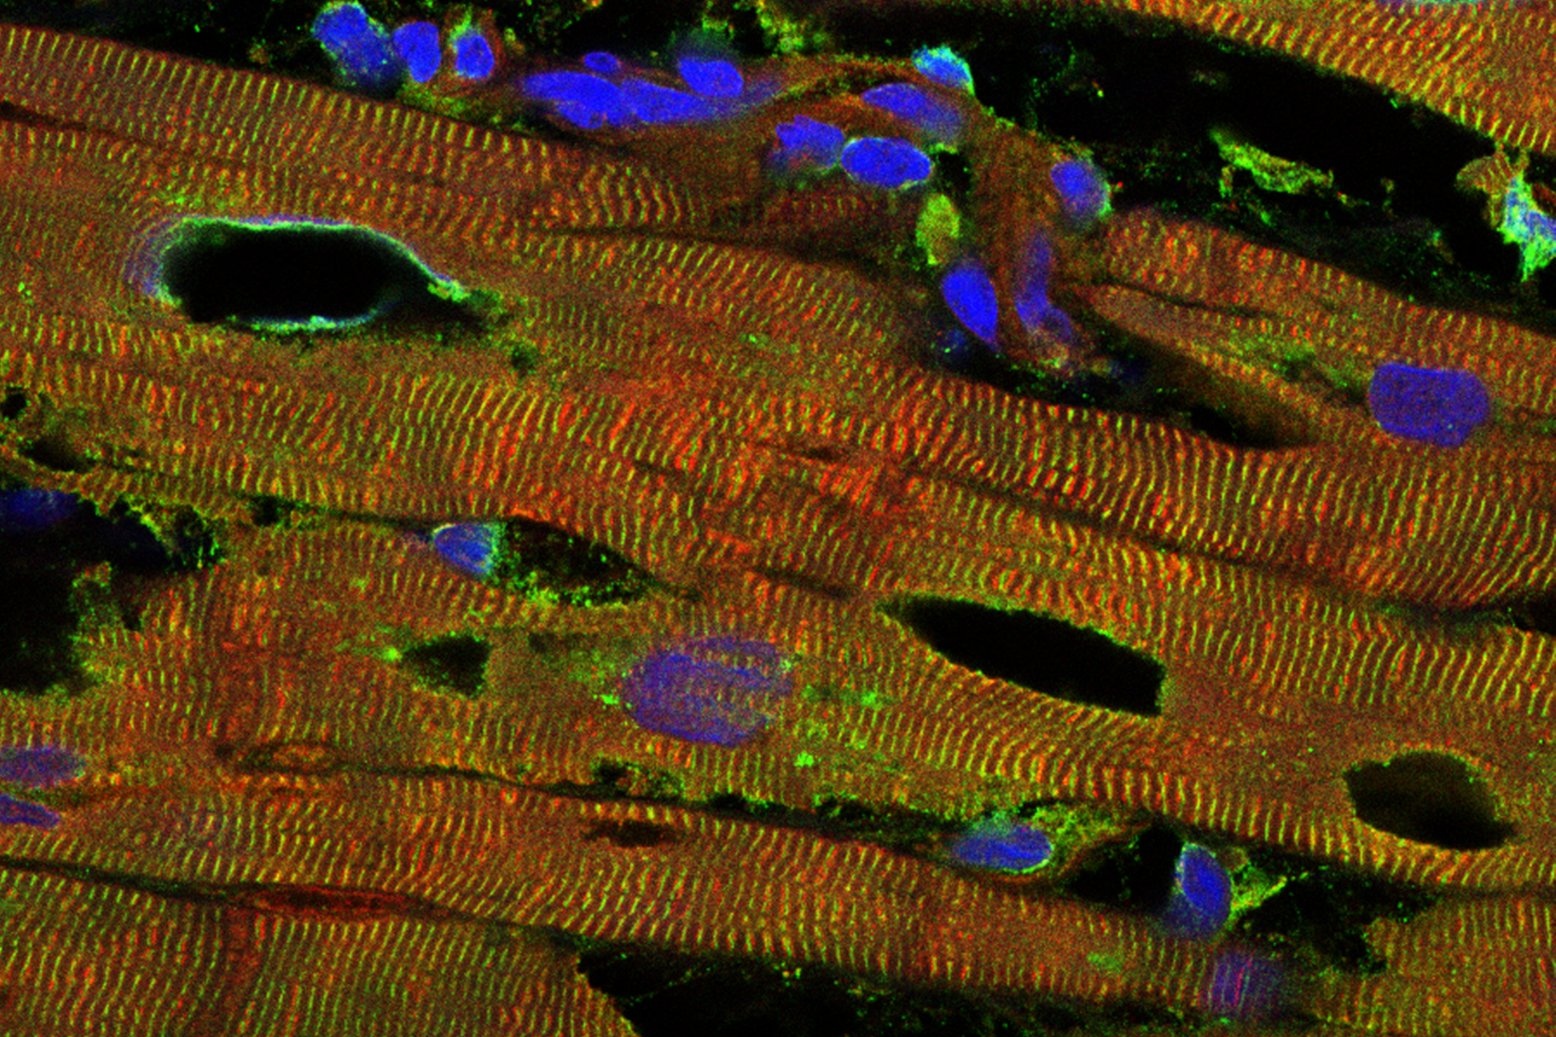

Wer am Fahrrad schon einmal einen Speichenbruch hatte oder mit dem Auto liegengeblieben ist, der weiß: mechanische Belastungen führen früher oder später zu Schäden, die repariert werden müssen. Das trifft auch auf die menschliche Muskulatur zu. „Bei jeder Bewegung werden Strukturproteine geschädigt und müssen ersetzt werden“, erklärt der Privatdozent Michael Hesse vom Institut für Physiologie der Universität Bonn, der die Studie zusammen mit seinem Kollegen Prof. Bernd Fleischmann geleitet hat.

Normalerweise werden die defekten Moleküle in der Zelle zerkleinert und ihre Bestandteile dann recycelt. Eine wichtige Rolle bei diesem komplexen Prozess spielt ein Protein namens BAG3. Wie wichtig, zeigen die Ergebnisse der neuen Studie: Die Forschenden konnten darin nachweisen, dass eine einzige Veränderung in der genetischen Bauanleitung von BAG3 zu einer tödlichen Erkrankung führt.

„Die Mutation führt dazu, dass BAG3 zusammen mit Partner-Proteinen unlösliche Komplexe bildet, die immer größer werden“, sagt Hesse. Dadurch kommen die Reparaturprozesse zum Erliegen – die Muskulatur wird immer weniger leistungsfähig. Zudem entsteht mit der Zeit eine toxische Protein-Anreicherung, die schließlich zum Tod der Muskelzelle führt. „Die Folgen werden meist zuerst am Herz sichtbar“, so Hesse. „Dort wird Muskel sukzessive durch Narbengewebe ersetzt. Dadurch sinkt die Elastizität des Herzens, bis es kaum noch Blut pumpen kann.“